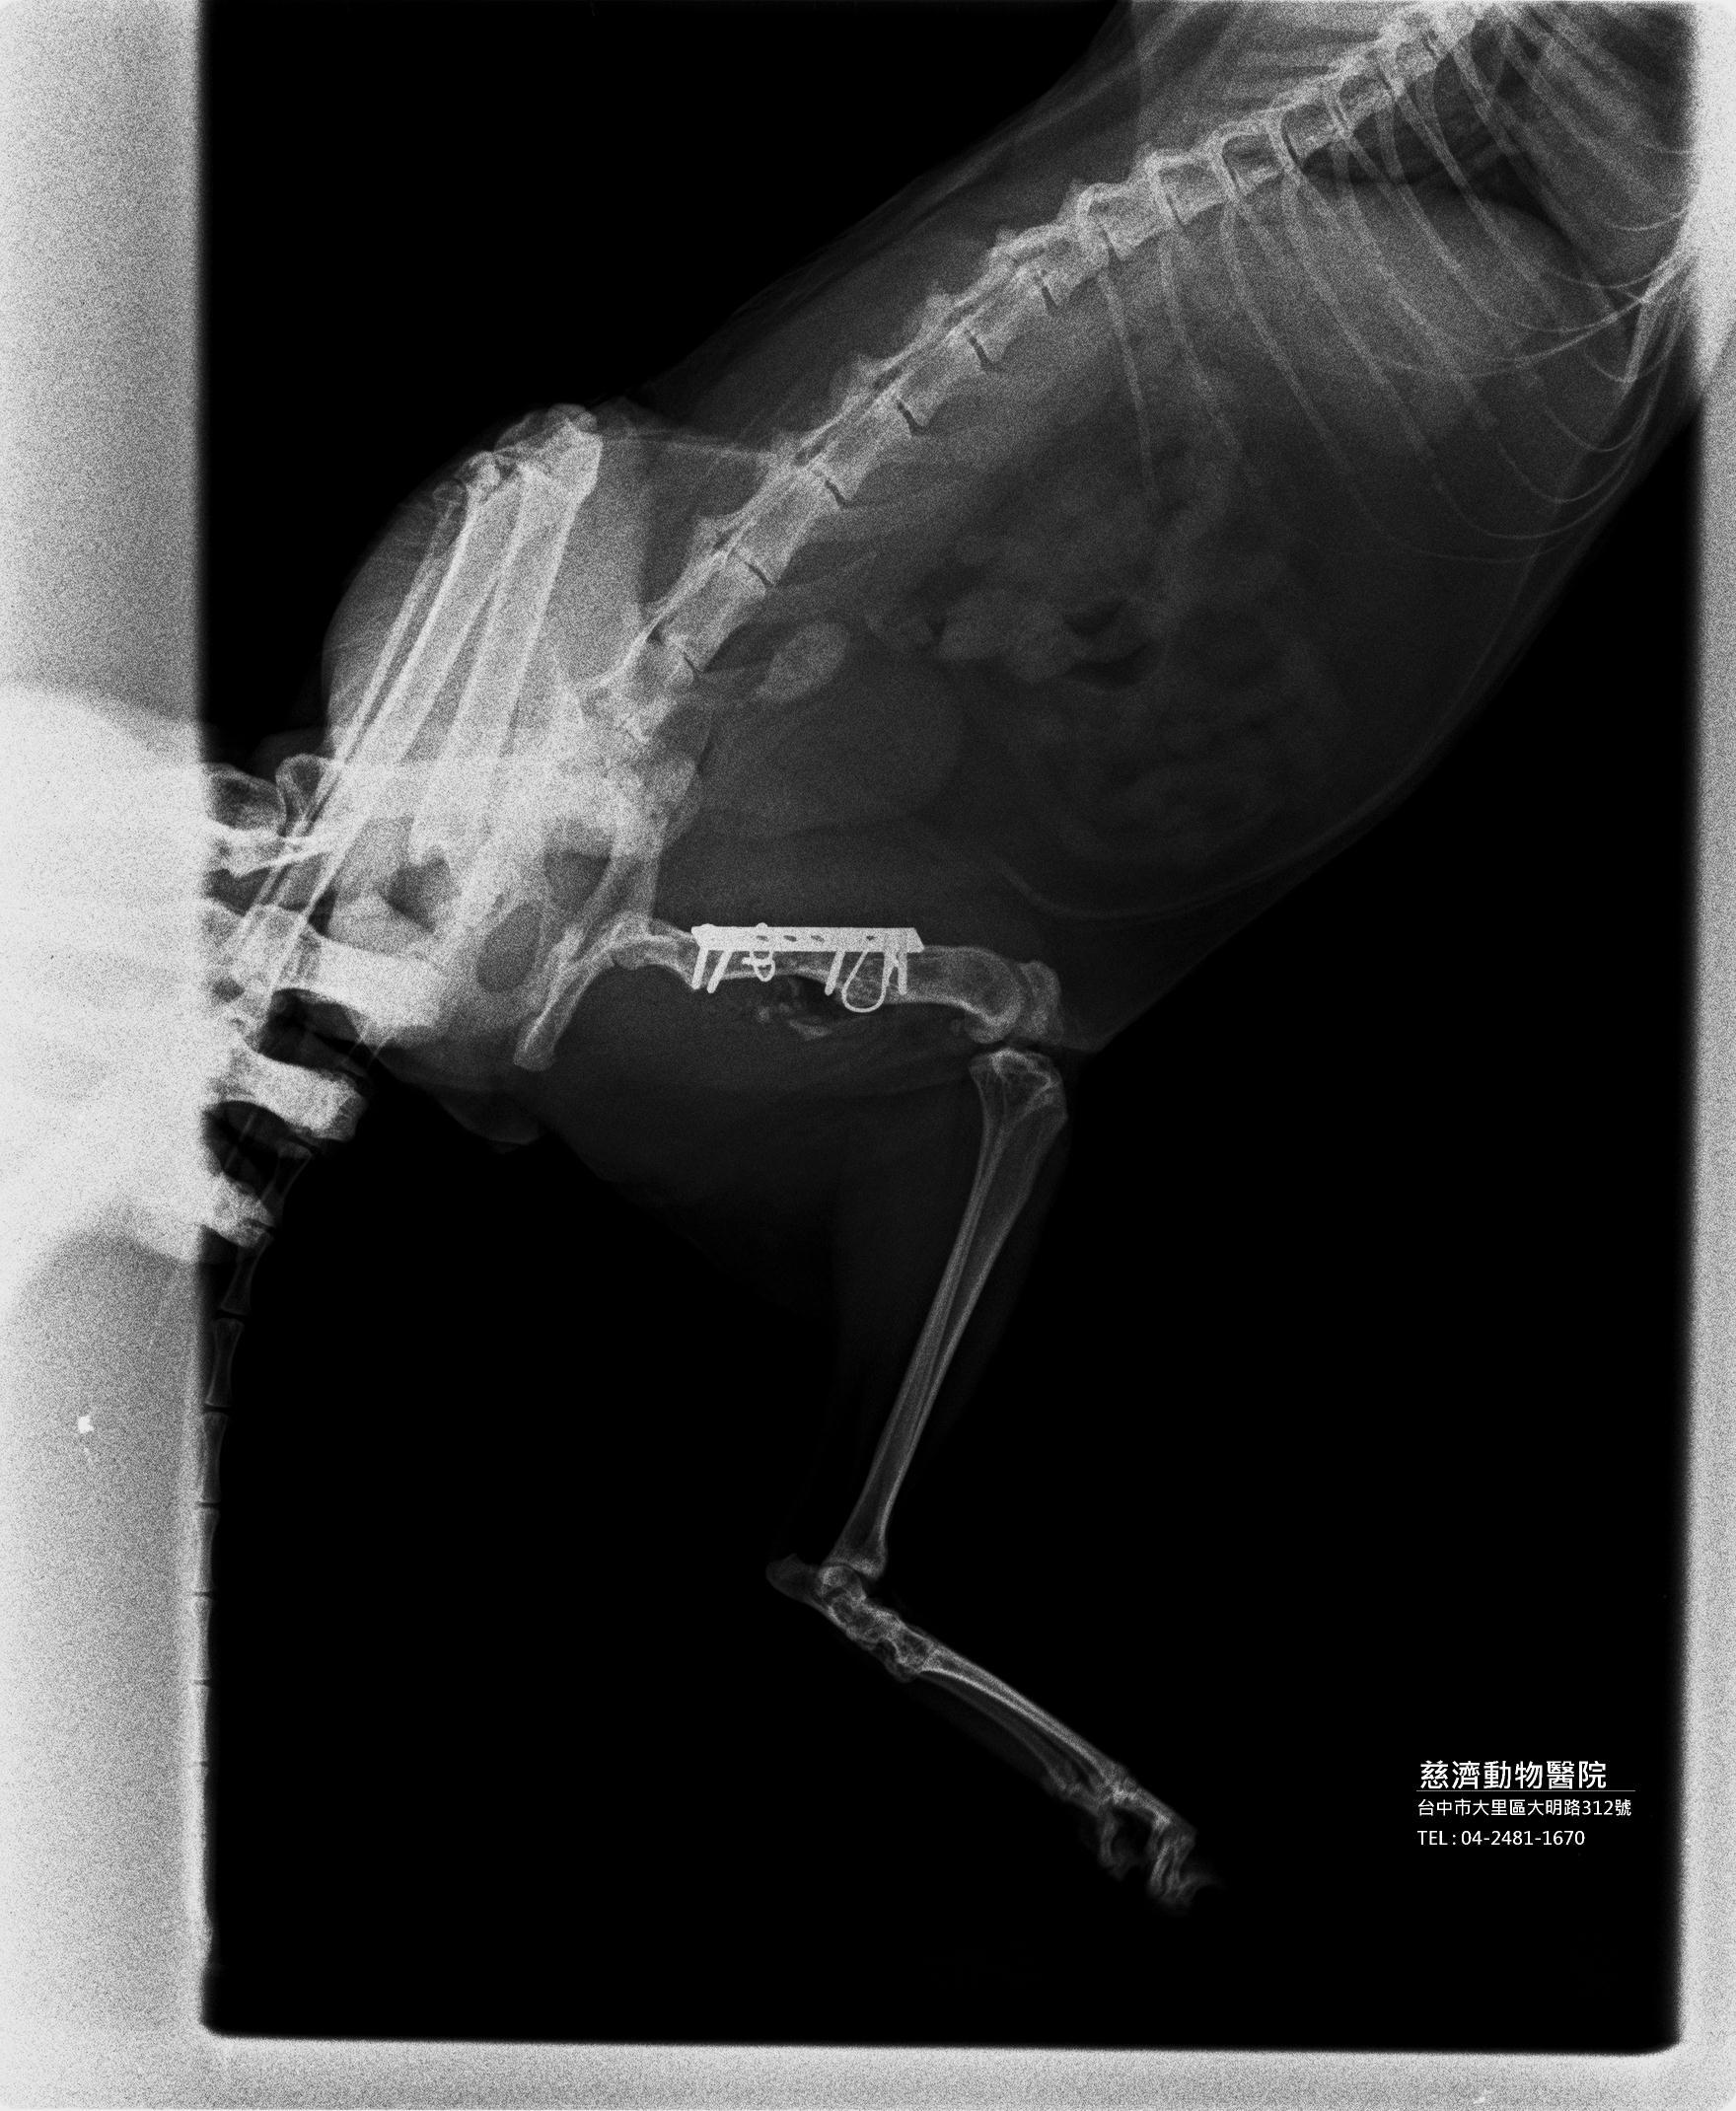

主題: 家門口食客喵喵腿再度斷掉 申請者姓名: 邱依如 花色: 申請日期: 2013-11-12 20:53:42 申請者部落格: 申請者臉書網址: 所在縣市/合作醫院: 台中市/慈濟動物醫院 治療費用: 15000元 需求人數: 17人 已結案 (2014-01-10 17:54:55) 報名人員: Bella(已付款)、鯉魚(已付款)、許韶娟(已付款)、蔡花枝 x2(已付款)、蔡花枝 x2、蔡花枝 x2、Patrick(已付款)、tau511(已付款)、Jason Chang(已付款)、ZLIN(已付款)、peggy(已付款)、momo(已付款)、小拉雅(已付款)、李坤財(已付款)、戴戴(已付款)、Jill Lee(已付款)、yuki x2(已付款)、 候補人員: 動物病情說明: 這隻喵喵是去年十月底曾經腿斷掉過申請醫助的浪貓

果不其然...原本斷掉的位置又斷掉了><

院長說喵喵本身骨頭就很脆弱(骨質酥鬆),所以會容易斷掉,這次手術完後真的要限制行動了><動物近況說明: 斷腿喵喵11/1出院了~狀況很好!!

不過他因為已經骨質蘇鬆(醫生說斷掉那個部位已經沒有骨髓了...),所以為了牠好,不能再讓牠去外面了!!!!